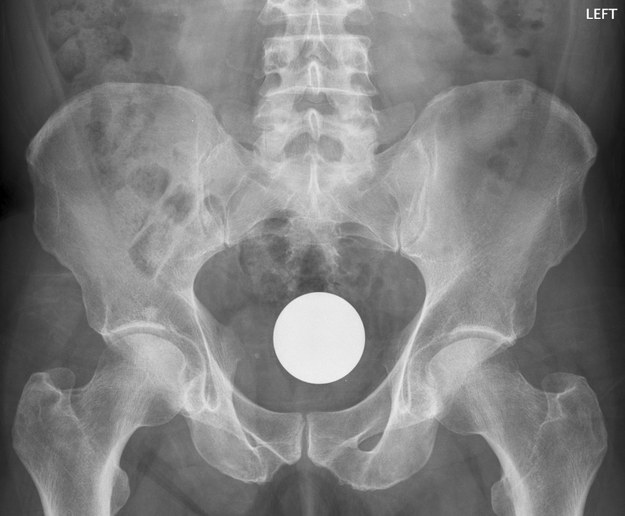

7. Μια μπάλα μπιλιάρδου